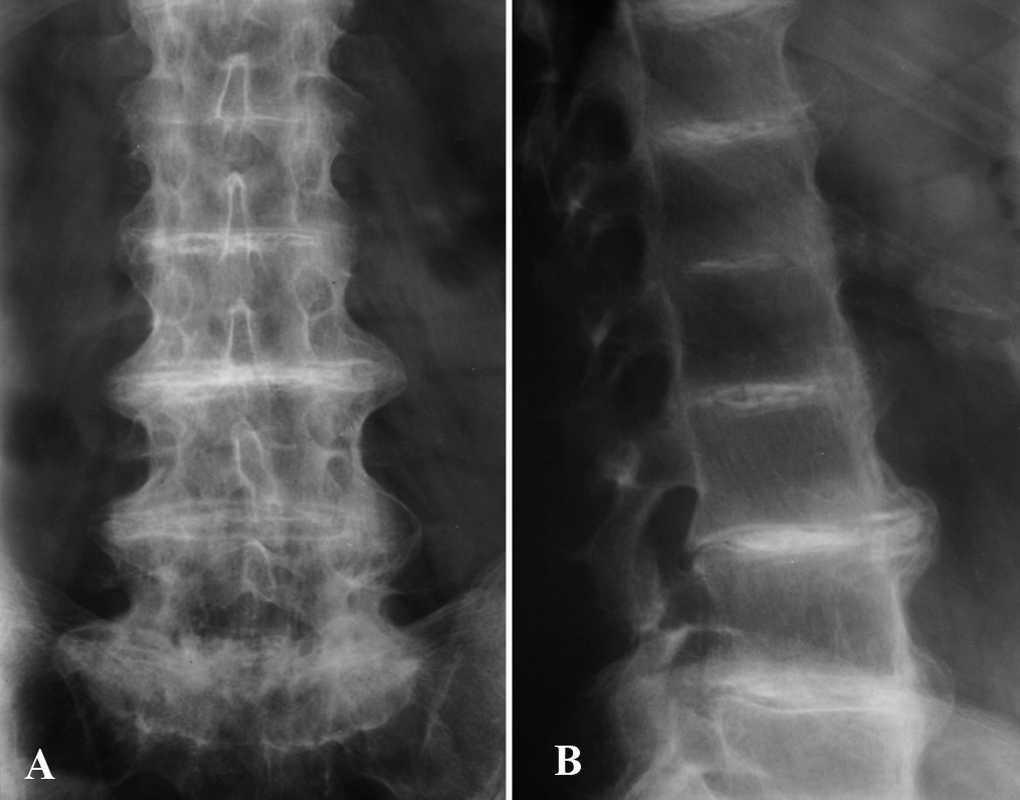

La hematimetría, recuento, fórmula, velocidad de sedimentación globular, y perfil bioquímico fueron normales o negativos. El perfil hepático mostró un leve aumento de transaminasas y gammaglutamiltransferasa, y en la ecografía se confirmó una esteatosis hepática de probable origen alcohólico. En orina de 24 h se demostró la presencia de ácido homogentísico muy elevado (5.616,0 mg/24 h [N ≤ 10,0 mg/24 h]). En el estudio radiográfico de la columna lumbar se apreciaron imágenes de osteoporosis difusa, calcificación del ligamento vertebral anterior, osteofitosis anterior, disminución de la altura de las vértebras lumbares y calcificación de todos los discos intervertebrales (fig. 5). La radiografía de la rodilla izquierda mostraba fenómenos de calcificación articular. Se realizó un estudio gammagráfico que demostró la presencia de un refuerzo intervertebral lumbar e imágenes de hipercaptación en la articulación del hombro y de la rodilla. Estos hallazgos gammagráficos en este paciente han sido previamente publicados por Cortés-Hernández et al 3. Se instauró tratamiento con complementos de vitamina C, (1.000 mg/día) y el paciente manifestó una discreta mejoría de sus síntomas articulares.

Fig. 5.--Radiografía simple anteroposterior (A) y lateral (B). Estrechamiento y calcificación de las articulaciones intervertebrales. Pérdida de la lordosis fisiológica.

La artropatía asociada a la ocronosis es de tipo degenerativo y carácter progresivo 2. Afecta principalmente al esqueleto axial y grandes articulaciones. Los síntomas musculoesqueléticos comienzan en forma de rigidez y dolor lumbar en un 50 % de los casos antes de los 30 años de edad y en casi todos los pacientes antes de los 40 7. Ocasionalmente se inicia rotura brusca del núcleo pulposo o en forma de monoartritis 8. El 50 % de los pacientes precisan prótesis articulares entre los 55 y 60 años de edad. La afectación tendinosa es frecuente (57 %). El depósito de pigmento en tendones conlleva su engrosamiento, y ocasiona tendinitis, calcificación y rotura de éstos 8. Es muy característico el engrosamiento y la rotura del tendón de Aquiles 11.

Los hallazgos radiológicos, como en nuestro paciente, son característicos si no patognomónicos 2. Hay un estrechamiento progresivo generalizado, calcificación, osificación, e incluso fusión de los espacios intervertebrales 8. A diferencia de las espondilitis, raramente se afectan las articulaciones sacroilíacas. En casos aislados se han realizado estudios gammagráficos con hallazgos equivalentes a cualquier otra artropatía degenerativa, aunque con algún rasgo característico 3.